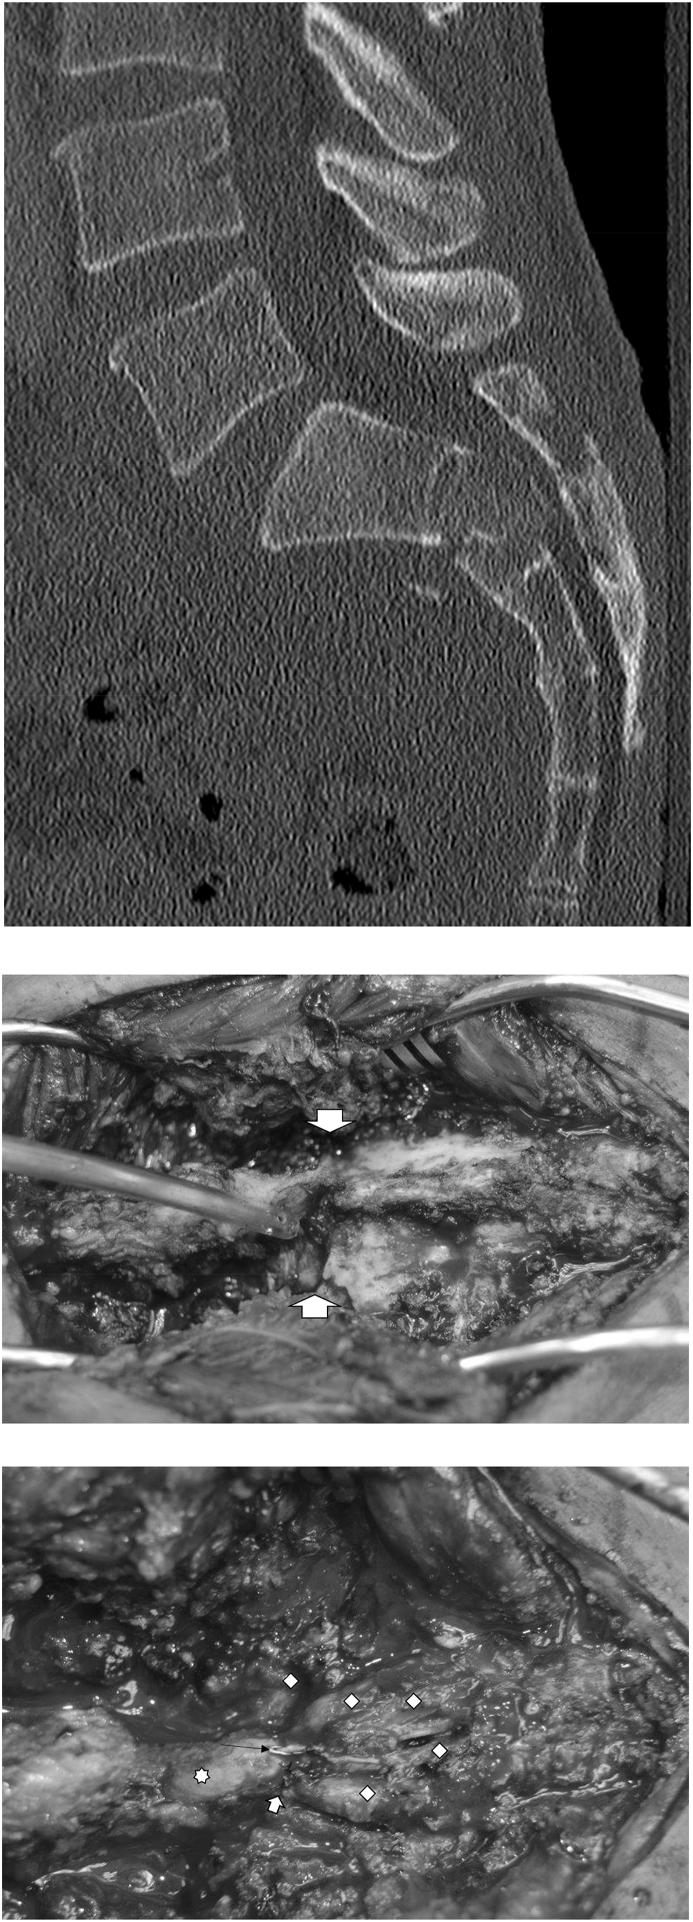

Laminectomy for acute transverse sacral fractures with compression of the cauda equina: A neurosurgical perspective.

Optimal management of transverse sacral fractures (TSF) remains inconclusive. These injuries may present with neurological deficits including cauda equina syndrome. We present our series of laminectomy for acute TSF with cauda equina compression.

A total of 9 patients (5 male and 4 female) underwent sacral laminectomy to decompress the cauda equina in the setting of acute high impact trauma. Surgeries were done early within a mean time of 5.9 days. All but one patient had symptomatic cauda equina syndrome. In one instance surgery was applied due to significant canal stenosis present on imaging in a patient with diminished mental status not allowing proper neurological examination. Torn sacral nerve roots were repaired directly when possible. All patients regained their neurological function related to the sacral cauda equina on follow up. The rate of surgical site infection (SSI) was 33%.

Acute early sacral laminectomy and nerve root repair as needed was effective in recovering bowel and bladder function in patients after high impact trauma and TSF with cauda equina compression. A high SSI rate may be reduced by delaying surgery past 1 week from trauma, but little data exists at this time for clear recommendations.